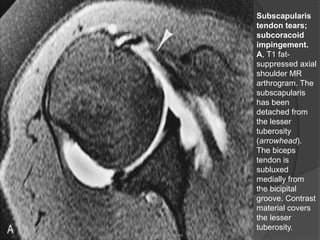

Subscapularis

tendon tears;

subcoracoid

impingement.

A, T1 fat-

suppressed axial

shoulder MR

arthrogram. The

has been

detached from

the lesser

tuberosity

(arrowhead).

The biceps

tendon is

subluxed

medially from

the bicipital

groove. Contrast

material covers

tuberosity.